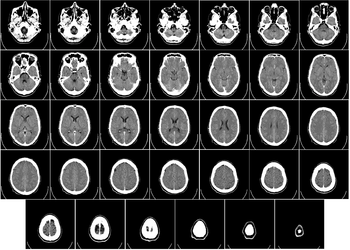

Although the human brain represents only 2% of the body weight, it receives 15% of the cardiac output, 20% of total body oxygen consumption, and 25% of total body glucose utilization.[34] The need to limit body weight has led to selection for a reduction of brain size in some species, such as bats, who need to be able to fly.[35] The brain mostly uses glucose for energy, and deprivation of glucose, as can happen in hypoglycemia, can result in loss of consciousness. The energy consumption of the brain does not vary greatly over time, but active regions of the cortex consume somewhat more energy than inactive regions: this fact forms the basis for the functional brain imaging methods PET and fMRI.[36] These are nuclear medicine, functional imaging techniques which produce a three-dimensional image of metabolic activity.

Structural and functional imaging

There are several methods for detecting brain activity changes using three-dimensional imaging of local changes in blood flow. The older methods are SPECT and PET, which depend on injection of radioactive tracers into the bloodstream. A newer method, functional magnetic resonance imaging (fMRI), has considerably better spatial resolution and involves no radioactivity.[46] Using the most powerful magnets currently available, fMRI can localize brain activity changes to regions as small as one cubic millimeter. The downside is that the temporal resolution is poor: when brain activity increases, the blood flow response is delayed by 1–5 seconds and lasts for at least 10 seconds. Thus, fMRI is a very useful tool for learning which brain regions are involved in a given behavior, but gives little information about the temporal dynamics of their responses. A major advantage for fMRI is that, because it is non-invasive, it can readily be used on human subjects. Another new non-invasive functional imaging method is functional near-infrared spectroscopy.